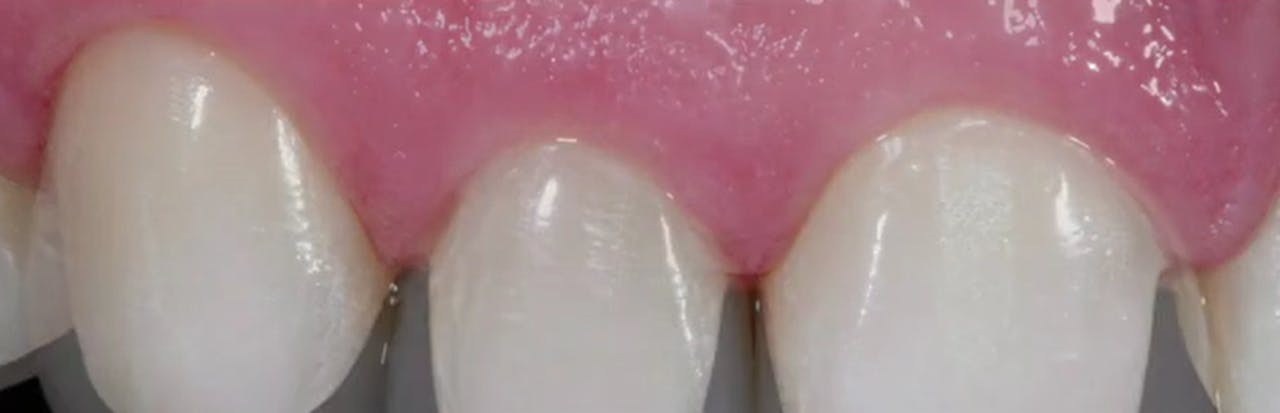

AllCeramic Solutions On Teeth & Implants gIDE Dental Institute Gide Dental Reviews • 550+ clinical videos on web and app • new dental videos added. Clinical videos, expert interviews, live broadcasts over. Evidence based video education at its best. Premiere provider of online dental education. Learn from the world's most trusted faculty and advance your skills with gide. Gide dental | 280 followers on linkedin. 31,762 likes · 74 talking about this. Gide Dental Reviews.